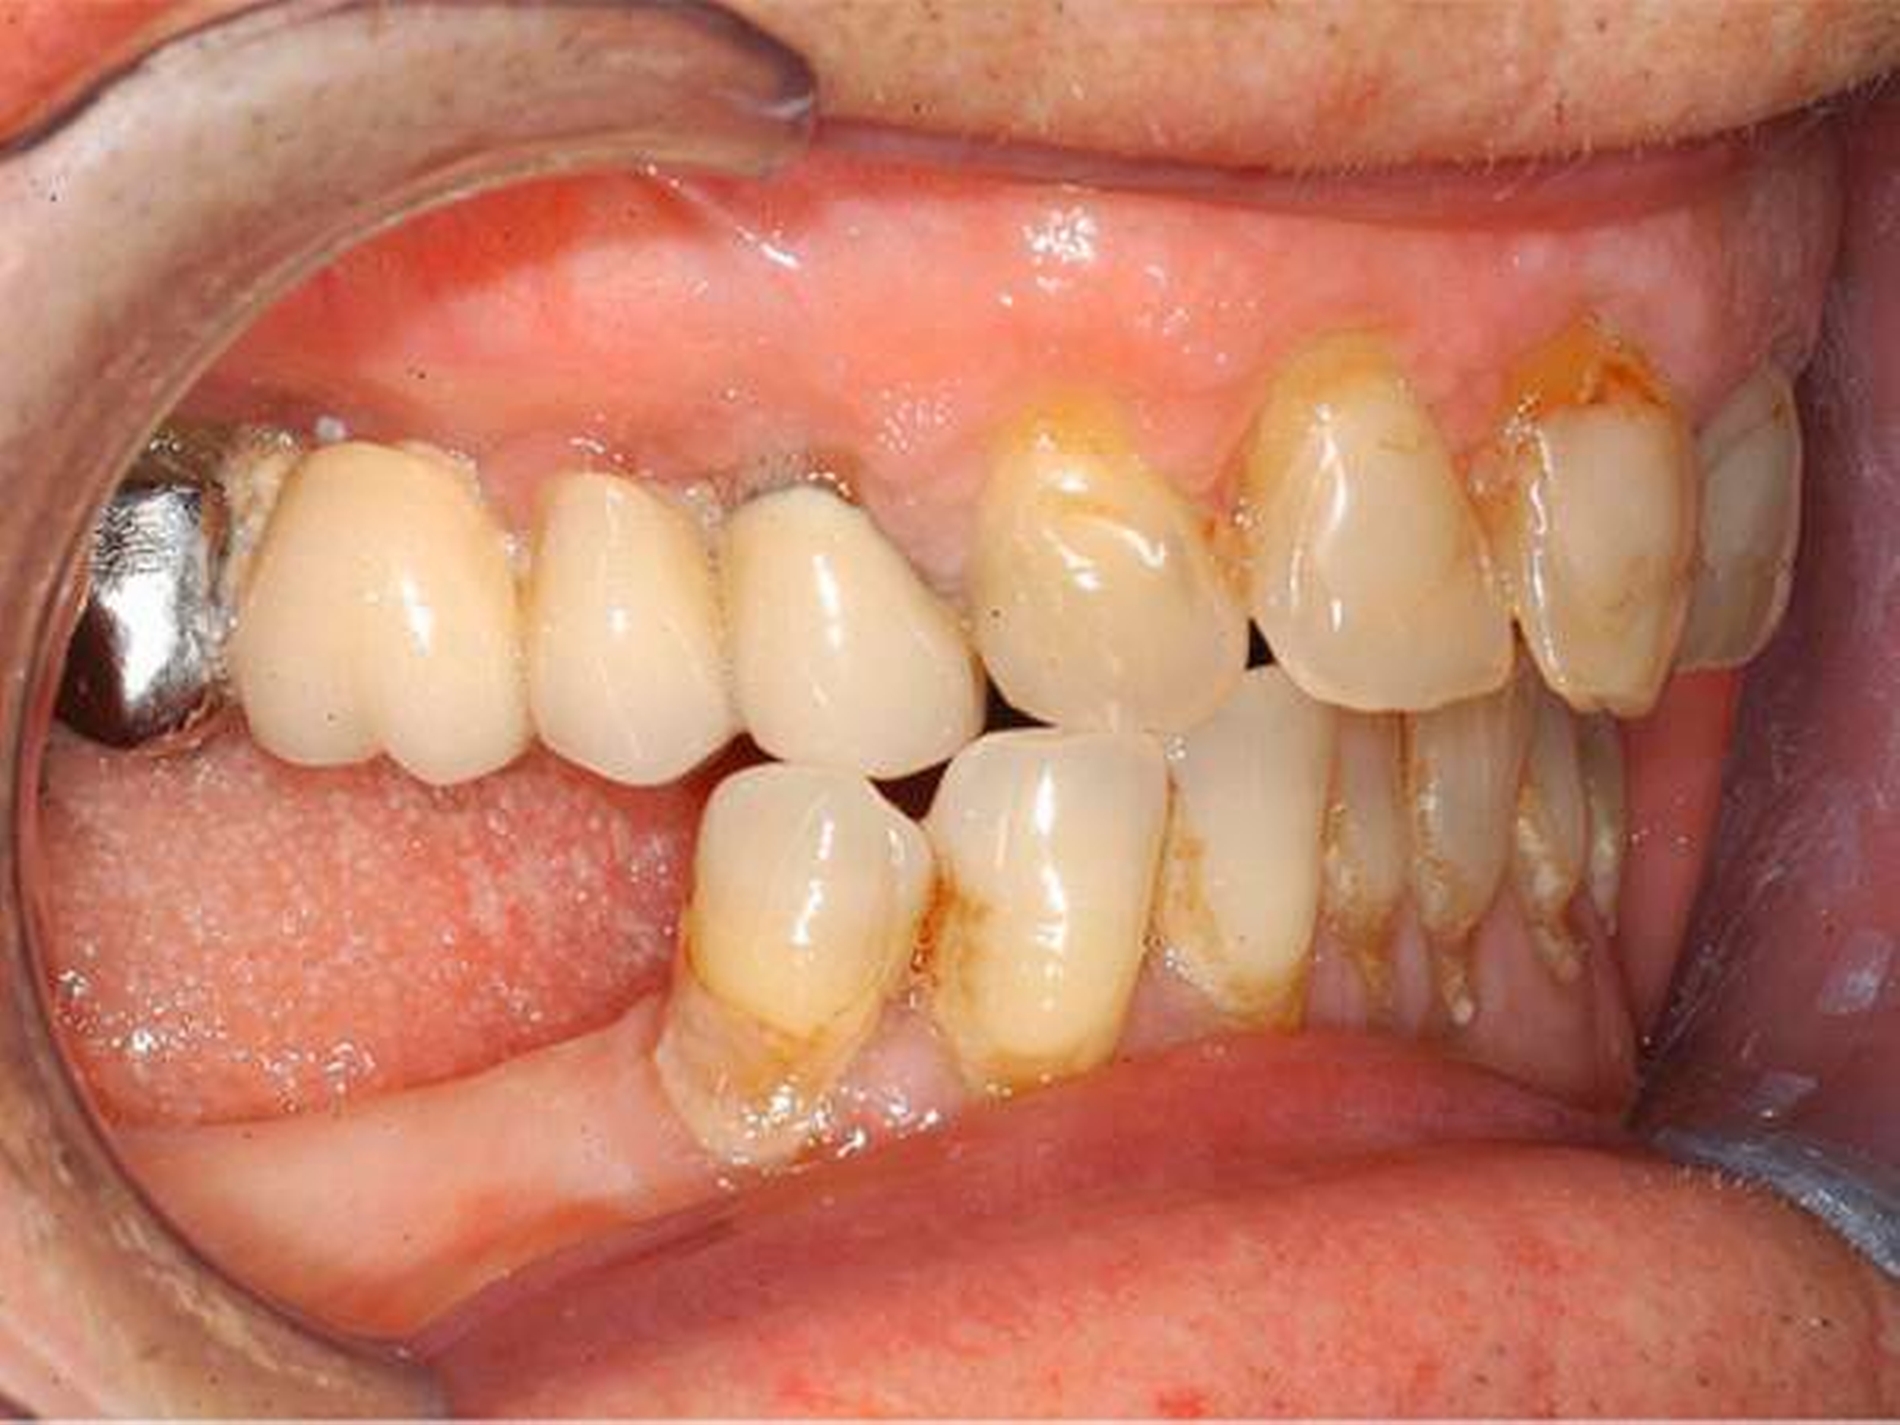

Bei der intraoralen Inspektion zeigte sich eine deutlich hyperplastische Gingiva mit Blutung auf Sondieren (BOP, Abbildungen 1 und 2). Da der Patientin die Handhabung einer Zahnbürste schwerfällt, zeigten sich auch deutliche Plaqueanlagerungen.

Aufgrund der schmerzhaften Gingivitis hatte die Patientin zudem Probleme mit der Nahrungsaufnahme. In der Panoramaschichtaufnahme (Abbildung 3) zeigte sich neben einem impaktierten Eckzahn ein Furkationsbefall der Molaren mit Konkrementen sowie ein altersentsprechender, generalisierter horizontaler Knochenabbau.

Dennoch erschien uns das Volumen der Gingiva nach bereits erfolgter geschlossener Parodontaltherapie ungewöhnlich.